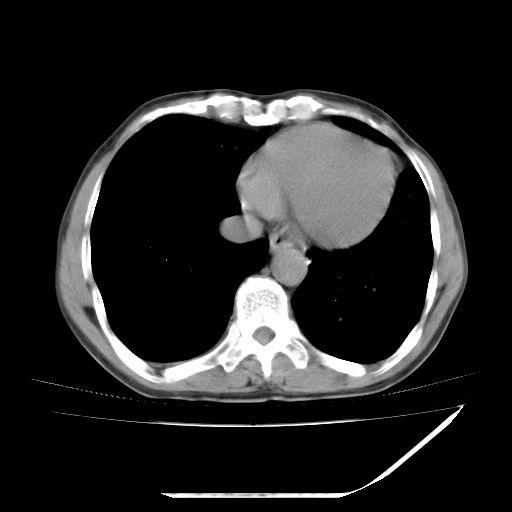

男,59岁,“结核性胸膜炎”30余年,胸部经常疼痛,多次x检查提示“肺部”炎症。腹部疼痛5日,b超提示:“肝内短管结石,余显示不清,建议进一步检查。”

两肺结核并右侧胸腔积液;脾脏、腹腔及腹膜后淋巴结结核[陈旧性];肝内胆管结石

胸部腹部都是结核(双肺。纵隔淋巴结,肝脏,脾脏,肠系膜)

两肺结核并右侧胸腔积液;脾脏、腹腔及腹膜后淋巴结结核[陈旧性];肝内胆管结石。直肠息肉?